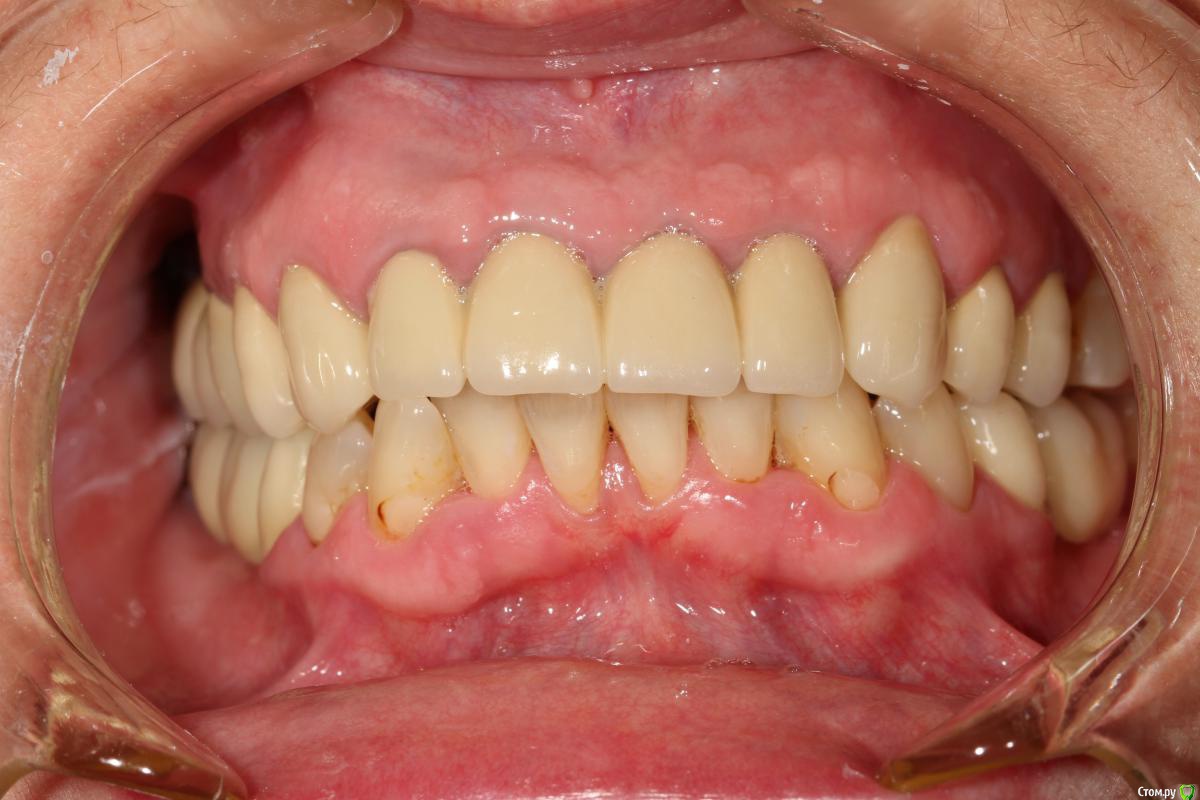

evodigit Опубликовано 21 мая, 2015 Поделиться Опубликовано 21 мая, 2015 Добрый день уважаемые коллеги, помогите советом.Пациентка два года назад была запротезирована у нас в клинике. Комбинированная работа, МК+ЦЛ. Через неделю пациентка обратилась с жалобами на разжевывание языка и щеки справа+ ощущение жжения языка. Коронки срезали, изготовили временные коронки в разных вариациях.( в общей сложности пациентка ходила с временными 3 месяца) Были изготовлены новые постоянные конструкции. Через полгода пациентка обратилась в клинику с жалобами на разжевывание языка. Была изготовлена миорелаксирующая каппа, после чего пациентка отмечает улучшение ситуации. Недавно пациентка обратилась в клинику опять с жалобами на разжевывание языка. Ситуация ухудшилась после того как пациентка реже стала носить каппу. До нашего лечения у пациентки стоял штампованный мост 10 лет. С чем может быть связана проблема? как ее решить? Заранее спасибо Ссылка на комментарий

chernov Опубликовано 23 мая, 2015 Поделиться Опубликовано 23 мая, 2015 evodigit вы сами себе противоречите про каппы.то есть положительная динамика(в первом сообщении),то нет.на какой цемент вы каппы ставите вообще не понятно...вообще эти отметины признак брукс компонента,скорее всего на н\ч в оласти 3-тих 4-рех зубов есть утолщение костной ткани.если да,то точно пациент бруксирует.а вследствии чего-это другой вопрос.возможно ваше протезирование и послужило толчком к этому(у пациента(ки) возможно горизонтальный тип жевания и так как ранее стояли плоские коронки было комфортно,а более выраженные новые конструкции организм пытается стереть,ИМХО,конечно).поэтому ищите причину,тем более пациентка отмечала улучшение после изготовления миорелаксирующей каппы,а если учесть,что каппа и срелаксировала мышцы и разомкнула зубы(дав горизонтальную свободу),то... Ссылка на комментарий